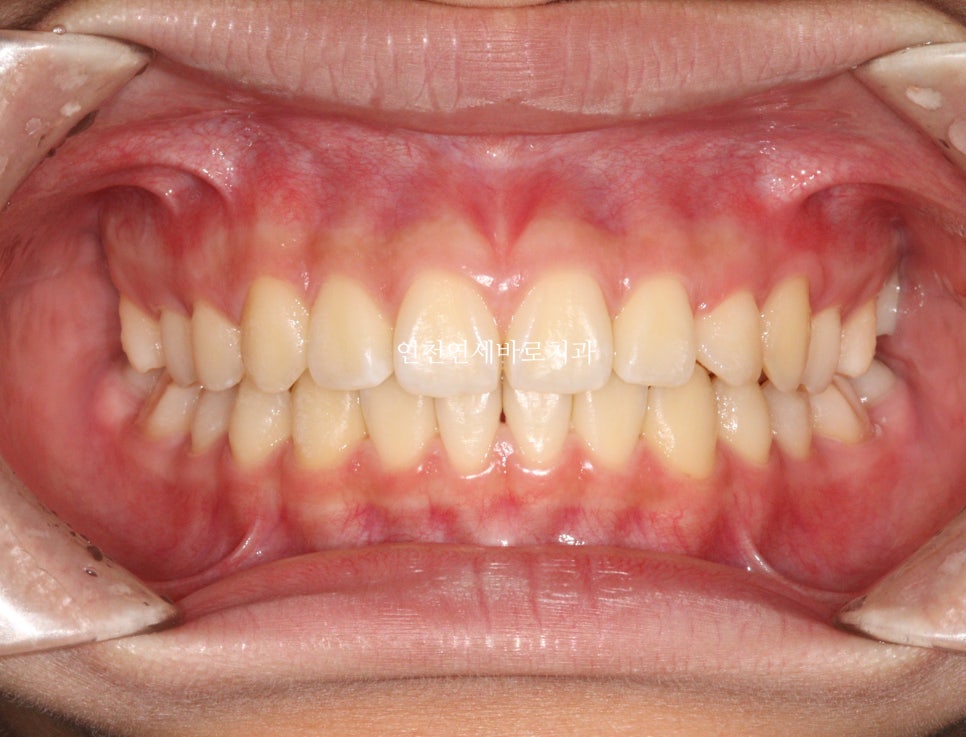

2024년 10월 – 치료 완료

중심선도 잘 맞고

교합도 양호합니다.

최후방 어금니는 맹출 중 입니다.